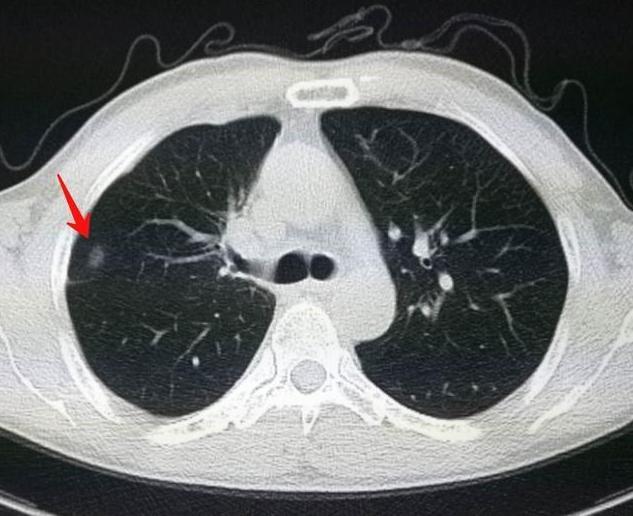

首先,我们需要了解什么是肺结节。肺结节是指在影像学上表现为直径≤3厘米的局灶性、类圆形、密度增高的实性或亚实性肺部阴影。根据大小,肺结节可分为微小结节(直径<5毫米)、小结节(直径5-10毫米)和肺结节(直径11-30毫米)。根据密度,可分为实性肺结节、磨玻璃密度结节和部分实性结节。值得注意的是,体检发现的肺结节中,95%都是良性的,大多数不需要特殊处理。

那么,我们如何通过CT影像初步判断肺结节的良恶性呢?以下是几个关键特征:

1. 大小:结节越大,恶性可能性越高。直径超过8毫米的结节需要特别关注。

2. 密度:部分实性结节的恶性概率最高,其次是磨玻璃密度结节,实性结节最低。

3. 边缘:光滑的边缘通常意味着良性,而分叶状或毛刺状边缘则提示恶性可能性。

5. 周围血管结构:恶性结节常有血管集束征。